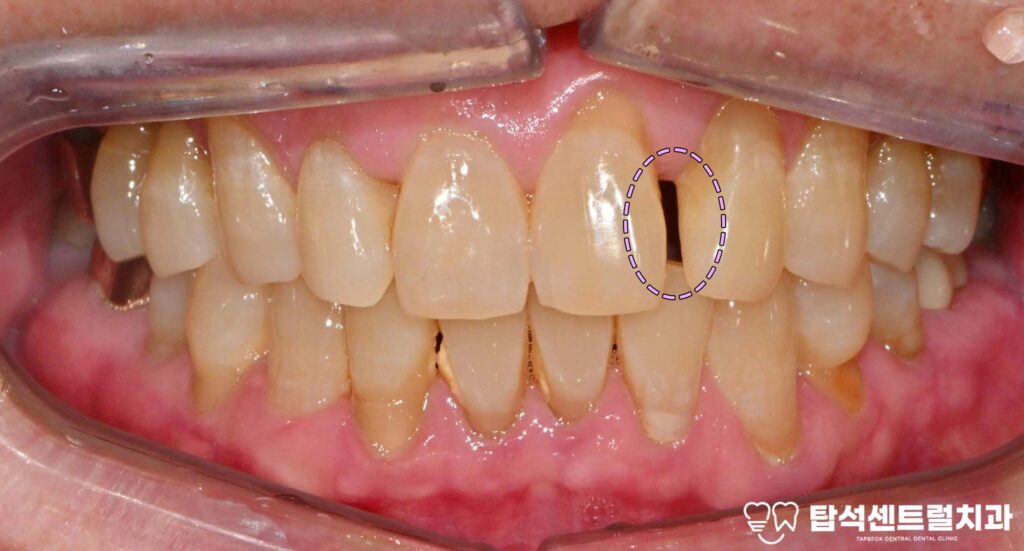

벌어진 앞니 사이 공간, 어떻게 개선할 수 있을까

벌어진 앞니 사이에 공간이 있으면

발음할 때 공기가 새어나가

의사소통에 어려움이 생길 수 있습니다.

혹은, 치아와 턱뼈의 크기가

균형을 이루지 못하는 경우

사이에 비어 있는 공간이 생깁니다.

벌어진 앞니 부위 결과와 관리 방법 소개

벌어진 윗니 사이 부분을 메운 후에는

자연스러운 형태로

회복되는 것을 확인할 수 있습니다.